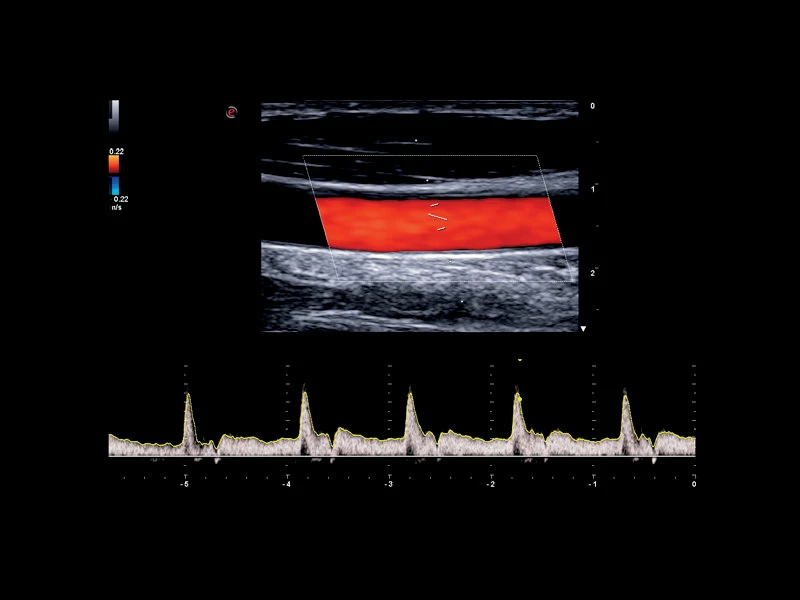

MyLab™C30 - Vertebral PW

MyLab™C30 - Vertebral PW